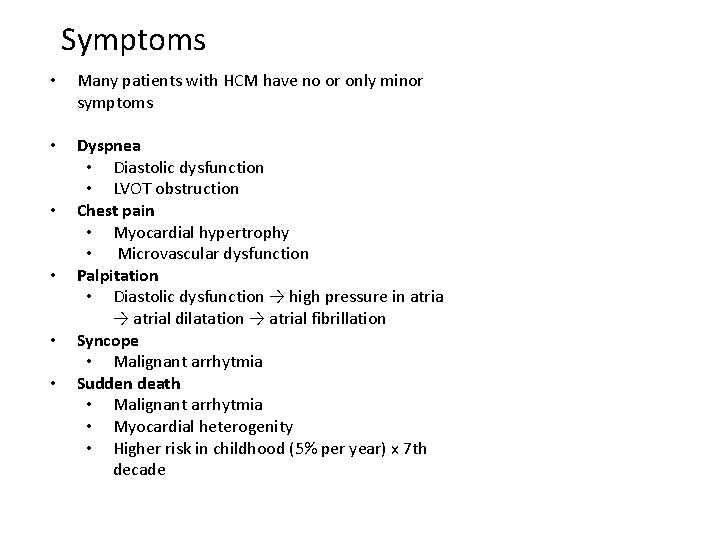

Symptoms • Many patients with HCM have no or only minor symptoms • Dyspnea • Diastolic dysfunction • LVOT obstruction Chest pain • Myocardial hypertrophy • Microvascular dysfunction Palpitation • Diastolic dysfunction → high pressure in atria → atrial dilatation → atrial fibrillation Syncope • Malignant arrhytmia Sudden death • Malignant arrhytmia • Myocardial heterogenity • Higher risk in childhood (5% per year) x 7 th decade • •